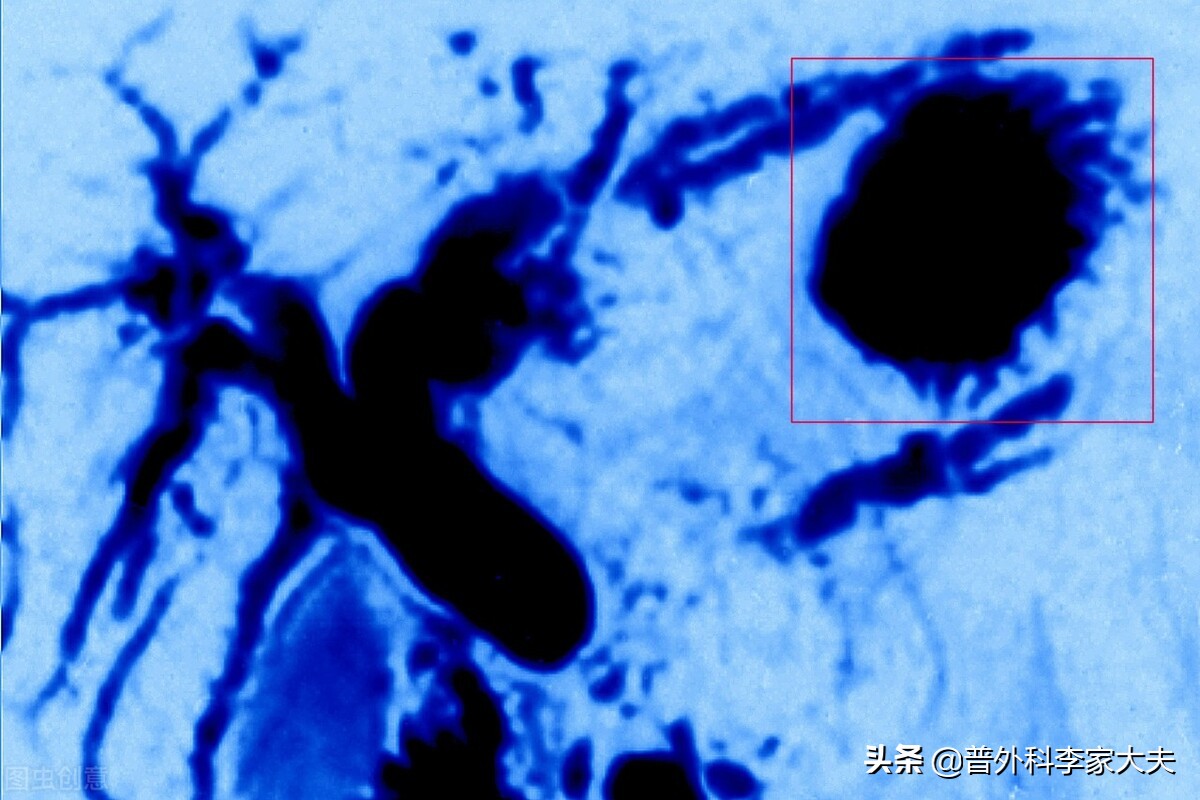

胰腺癌三维成像